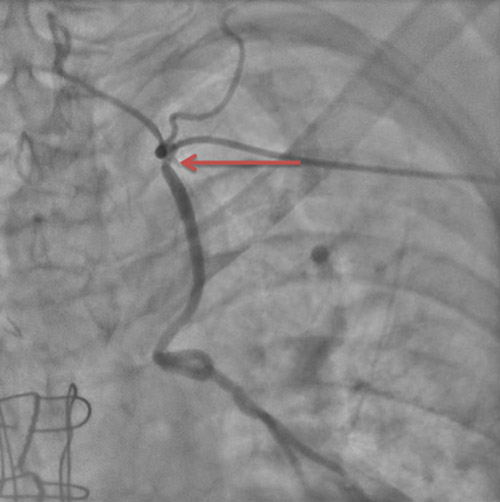

Il existait un doute sur une sténose à l’ostium de la mammaire interne gauche, avec un rétrécissement estimé visuellement à 50%, avec une légère ventricularisation des pressions lors de l’intubation sélective.

Images 5 : sténose intermédiaire de l’ostium de la mammaire interne gauche